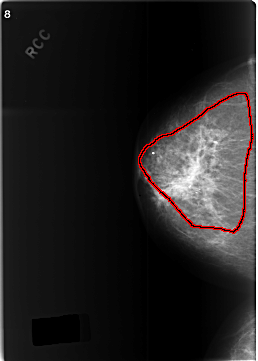

FILE: C_0342_1.RIGHT_CC.OVERLAY

TOTAL_ABNORMALITIES 1

ABNORMALITY 1

LESION_TYPE MASS SHAPE ASYMMETRIC_BREAST_TISSUE MARGINS ILL_DEFINED

ASSESSMENT 5

SUBTLETY 5

PATHOLOGY MALIGNANT

TOTAL_OUTLINES 1

BOUNDARY